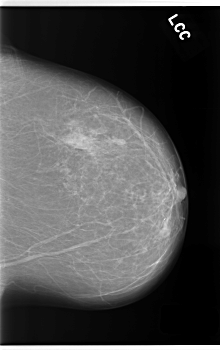

C_0253_1.LEFT_CC

LEFT_CC LINES 5936 PIXELS_PER_LINE 3728 BITS_PER_PIXEL 12 RESOLUTION 50 NON_OVERLAY